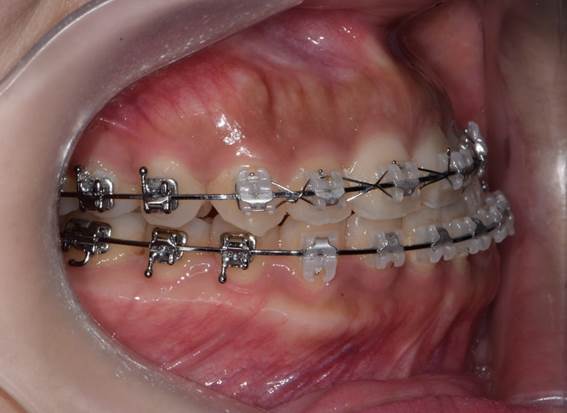

구내 우측모.jpg

구내 정모.jpg

구내 좌측모.jpg

위턱 치아의 중심선에 비해 아래턱 치아의 중심선이 좌측으로 돌아가 있다.

위 환자는 안면 비대칭이 있는 환자로, 처음 병원에 내원한 후 수술 전 교정이 필요하다고 진단을 받고, 1년 가까이 교정을 받고 수술을 위해 다시 내원한 환자입니다.